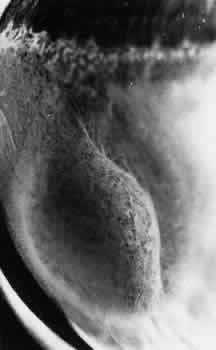

TYPICAL CYSTOID DEGENERATION

The most common form of degeneration of the peripheral retina is typical cystoid degeneration. Spaces develop in the outer plexiform and inner nuclear layers and coalesce to form interlacing tunnels; they are separated by pillars that extend from the inner to the outer retinal layers, giving the inner surface a uniformly stippled appearance (Fig. 15). The stippled depressions correspond to retinal pillars; the intervening rounded domes result from the intraretinal cystoid spaces.9 Degeneration begins at the ora serrata, particularly at the base of dentate processes, and extends posteriorly and circumferentially to form a band that may encircle the eye and reach from the ora serrata to the equator (Fig. 16).

Fig. 16. Typical and reticular cystoid degeneration found immediately behind the ora serrata and about enclosed ora bay near cut edge of calotte. Posteriorly, note the conspicuous vascular pattern of degeneration (seen as gray background), finely stippled surface pattern, and angular free margins (related to limitation by surface vessels).

This degenerative process may be noted in infants at 1 year of age; it is always present in both eyes of patients over 8 years of age, usually increases in area with advancing age, and is most extensive in the superior and temporal quadrants (see Table 3).10,11